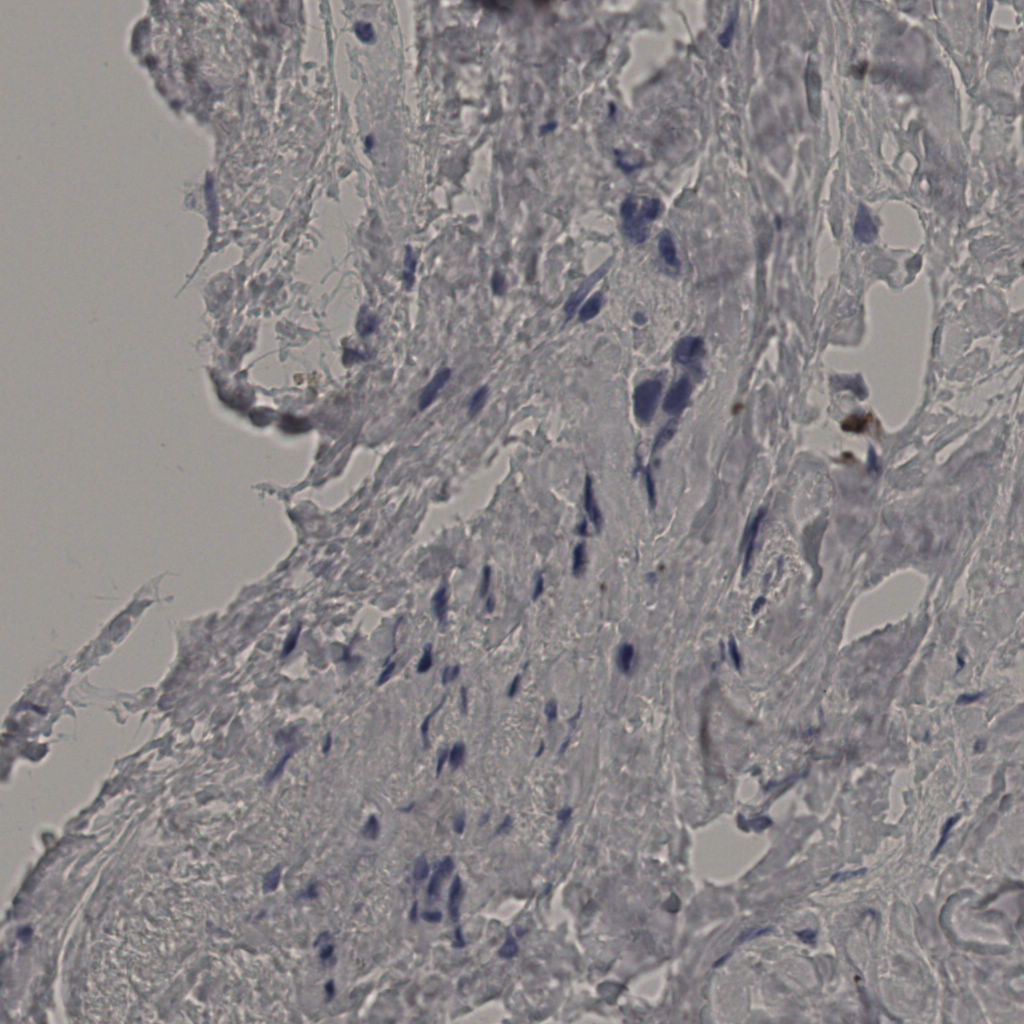

标记后

标记前